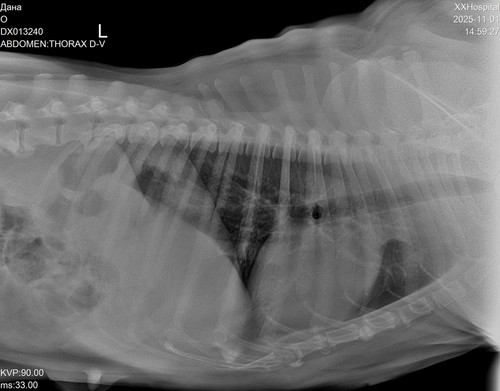

Дама в возрасте, лет 8-9. Вся в новообразованиях. В том числе раздут один сосок, откуда выделяется жидкость.